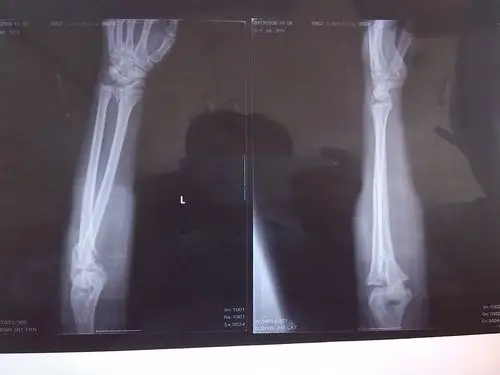

左上肢肱骨骨折术后三月余

关节上肢关节多发骨折

恐怖!澳大利亚骑师意外坠马 手臂骨折呈曲线状